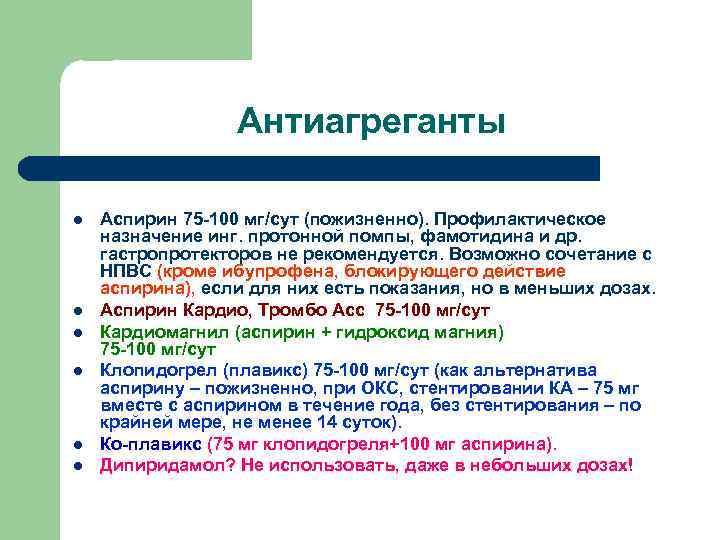

Антиагреганты l l l Аспирин 75 -100 мг/сут (пожизненно). Профилактическое назначение инг. протонной помпы, фамотидина и др. гастропротекторов не рекомендуется. Возможно сочетание с НПВС (кроме ибупрофена, блокирующего действие аспирина), если для них есть показания, но в меньших дозах. Аспирин Кардио, Тромбо Асс 75 -100 мг/сут Кардиомагнил (аспирин + гидроксид магния) 75 -100 мг/сут Клопидогрел (плавикс) 75 -100 мг/сут (как альтернатива аспирину – пожизненно, при ОКС, стентировании КА – 75 мг вместе с аспирином в течение года, без стентирования – по крайней мере, не менее 14 суток). Ко-плавикс (75 мг клопидогреля+100 мг аспирина). Дипиридамол? Не использовать, даже в небольших дозах!